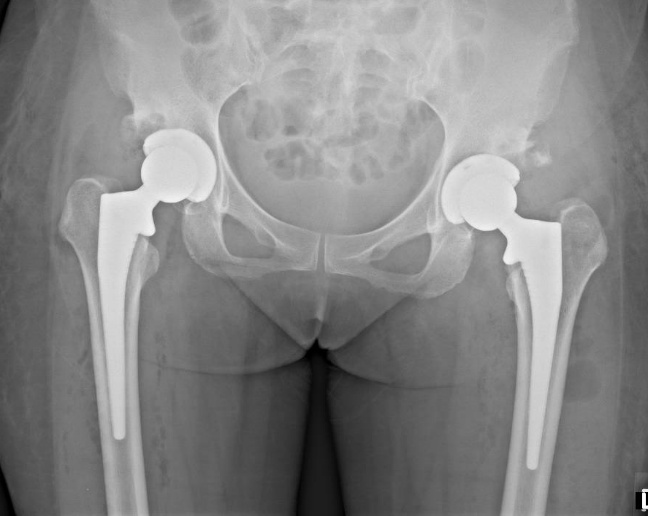

何时需要全髋关节置换术?

当关节损伤不可逆且保守或再生治疗无法缓解时,需考虑全髋关节置换术(THR)。主要适应症包括:

- 严重疼痛:持续疼痛影响睡眠、日常活动或行走,其他治疗无效。

- 骨与骨直接摩擦:X光或MRI确认的晚期软骨丧失(第4阶段OA)。

- 股骨头变形:因骨坏死、严重OA或髋关节发育不良等导致股骨头结构破坏。变形会阻碍关节活动,引发摩擦、不稳定及不可逆损伤。

- 功能丧失:因僵硬或无力无法行走、爬楼梯或完成基本动作。

- 关节畸形:髋部对齐异常或下肢长度差异。

什么是全髋关节置换术?

THR通过手术切除受损的股骨头和髋臼(关节窝),替换为人工假体。现代技术和材料使超过95%的患者恢复无痛且稳定的关节功能。